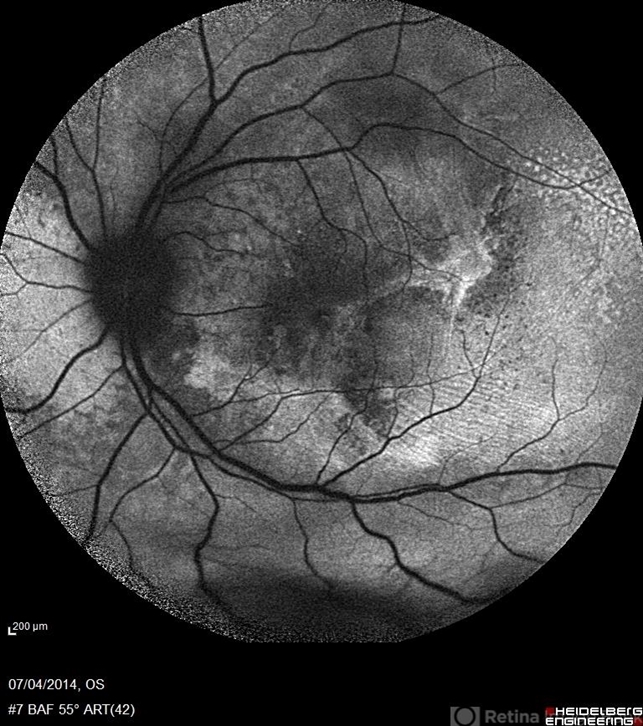

- multifocal central serous chorioretinopathy (CSCR), fundus autofluorescence (FAF)

- Blue auto fluorescence fundus photograph a 38-year-old man with multifocal CSR and inferior exudative retinal detachment on both eyes (Harada Syndrome). This patient has underwent a photocoagulation laser on both eyes.